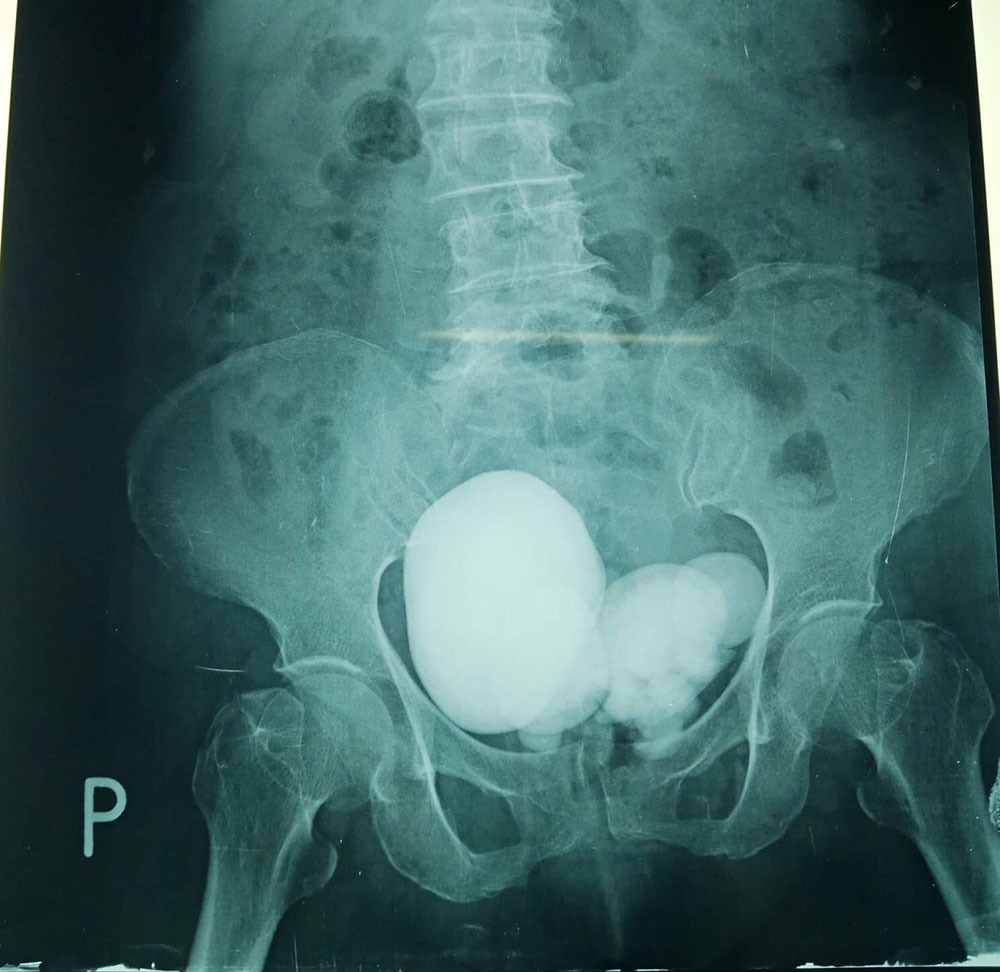

| Hình ảnh sỏi bàng quang khổng lồ trong người cụ bà 84 tuổi |

Tại đây, kết quả siêu âm bụng cho thấy bệnh nhân có sỏi bàng quang to, chụp X-Quang và CT Scan thấy thận (P) ứ nước độ I, niệu quản (P) dãn đến bàng quang, rất nhiều sỏi chiếm hết lòng bàng quang.

Trong đó, có viên sỏi nằm cạnh phải bàng quang to khoảng 12cm nằm trong túi thừa bàng quang, thận phải ứ nước độ I nhu mô thận phải còn dầy.

Trong lúc phẫu thuật, các bác sĩ đã lấy ra khoảng 15 viên sỏi từ 3cm - 8cm; có một viên sỏi rất to khoảng 12cm nằm trong một túi thừa bên phải, cạnh bàng quang đè lên niệu quản vùng chậu phải, gây ứ nước thận, mô xung quanh túi thừa rất dính do viêm, bóc tách túi thừa lấy sỏi 12cm ra bên trong có ít mủ và cặn trắng.